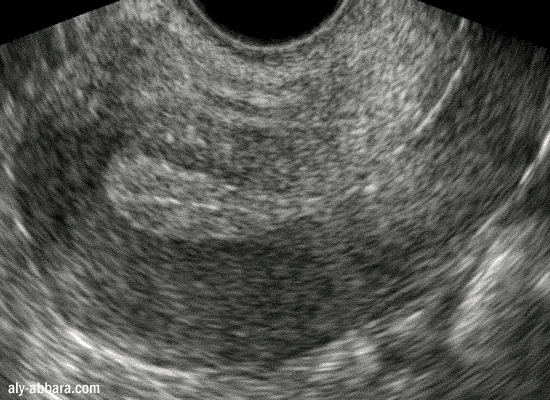

Hypotrophie de l'endomètre chez une patiente sous

contraception par progestatif normo-dosées et se plaignant de métrorragie

Endomètre de 2,5 mm d'épaisseur au 12ème jour du cycle menstruel